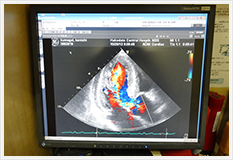

超音波検査

超音波とは人間の耳に聴こえない高い周波数の音のことです。

体表から超音波をあて、臓器や組織に当たって反射したものを画像処理し、身体の状態を調べる検査です。

心臓・腹部・血管の超音波検査を行っています。

心臓超音波検査

心臓の大きさ、動き、心臓の弁の状態や血行状態などを観察する検査です。

心筋梗塞、弁膜症、先天性心疾患などの有無を観察することができます。

腹部超音波検査

肝臓、胆嚢、腎臓、膵臓、脾臓などの消化器を中心に観察しています。

血管超音波検査

血管壁の状態を観察したり、血流情報を観察します。

主な部位は腎動脈、頸動脈、下肢動静脈などです。